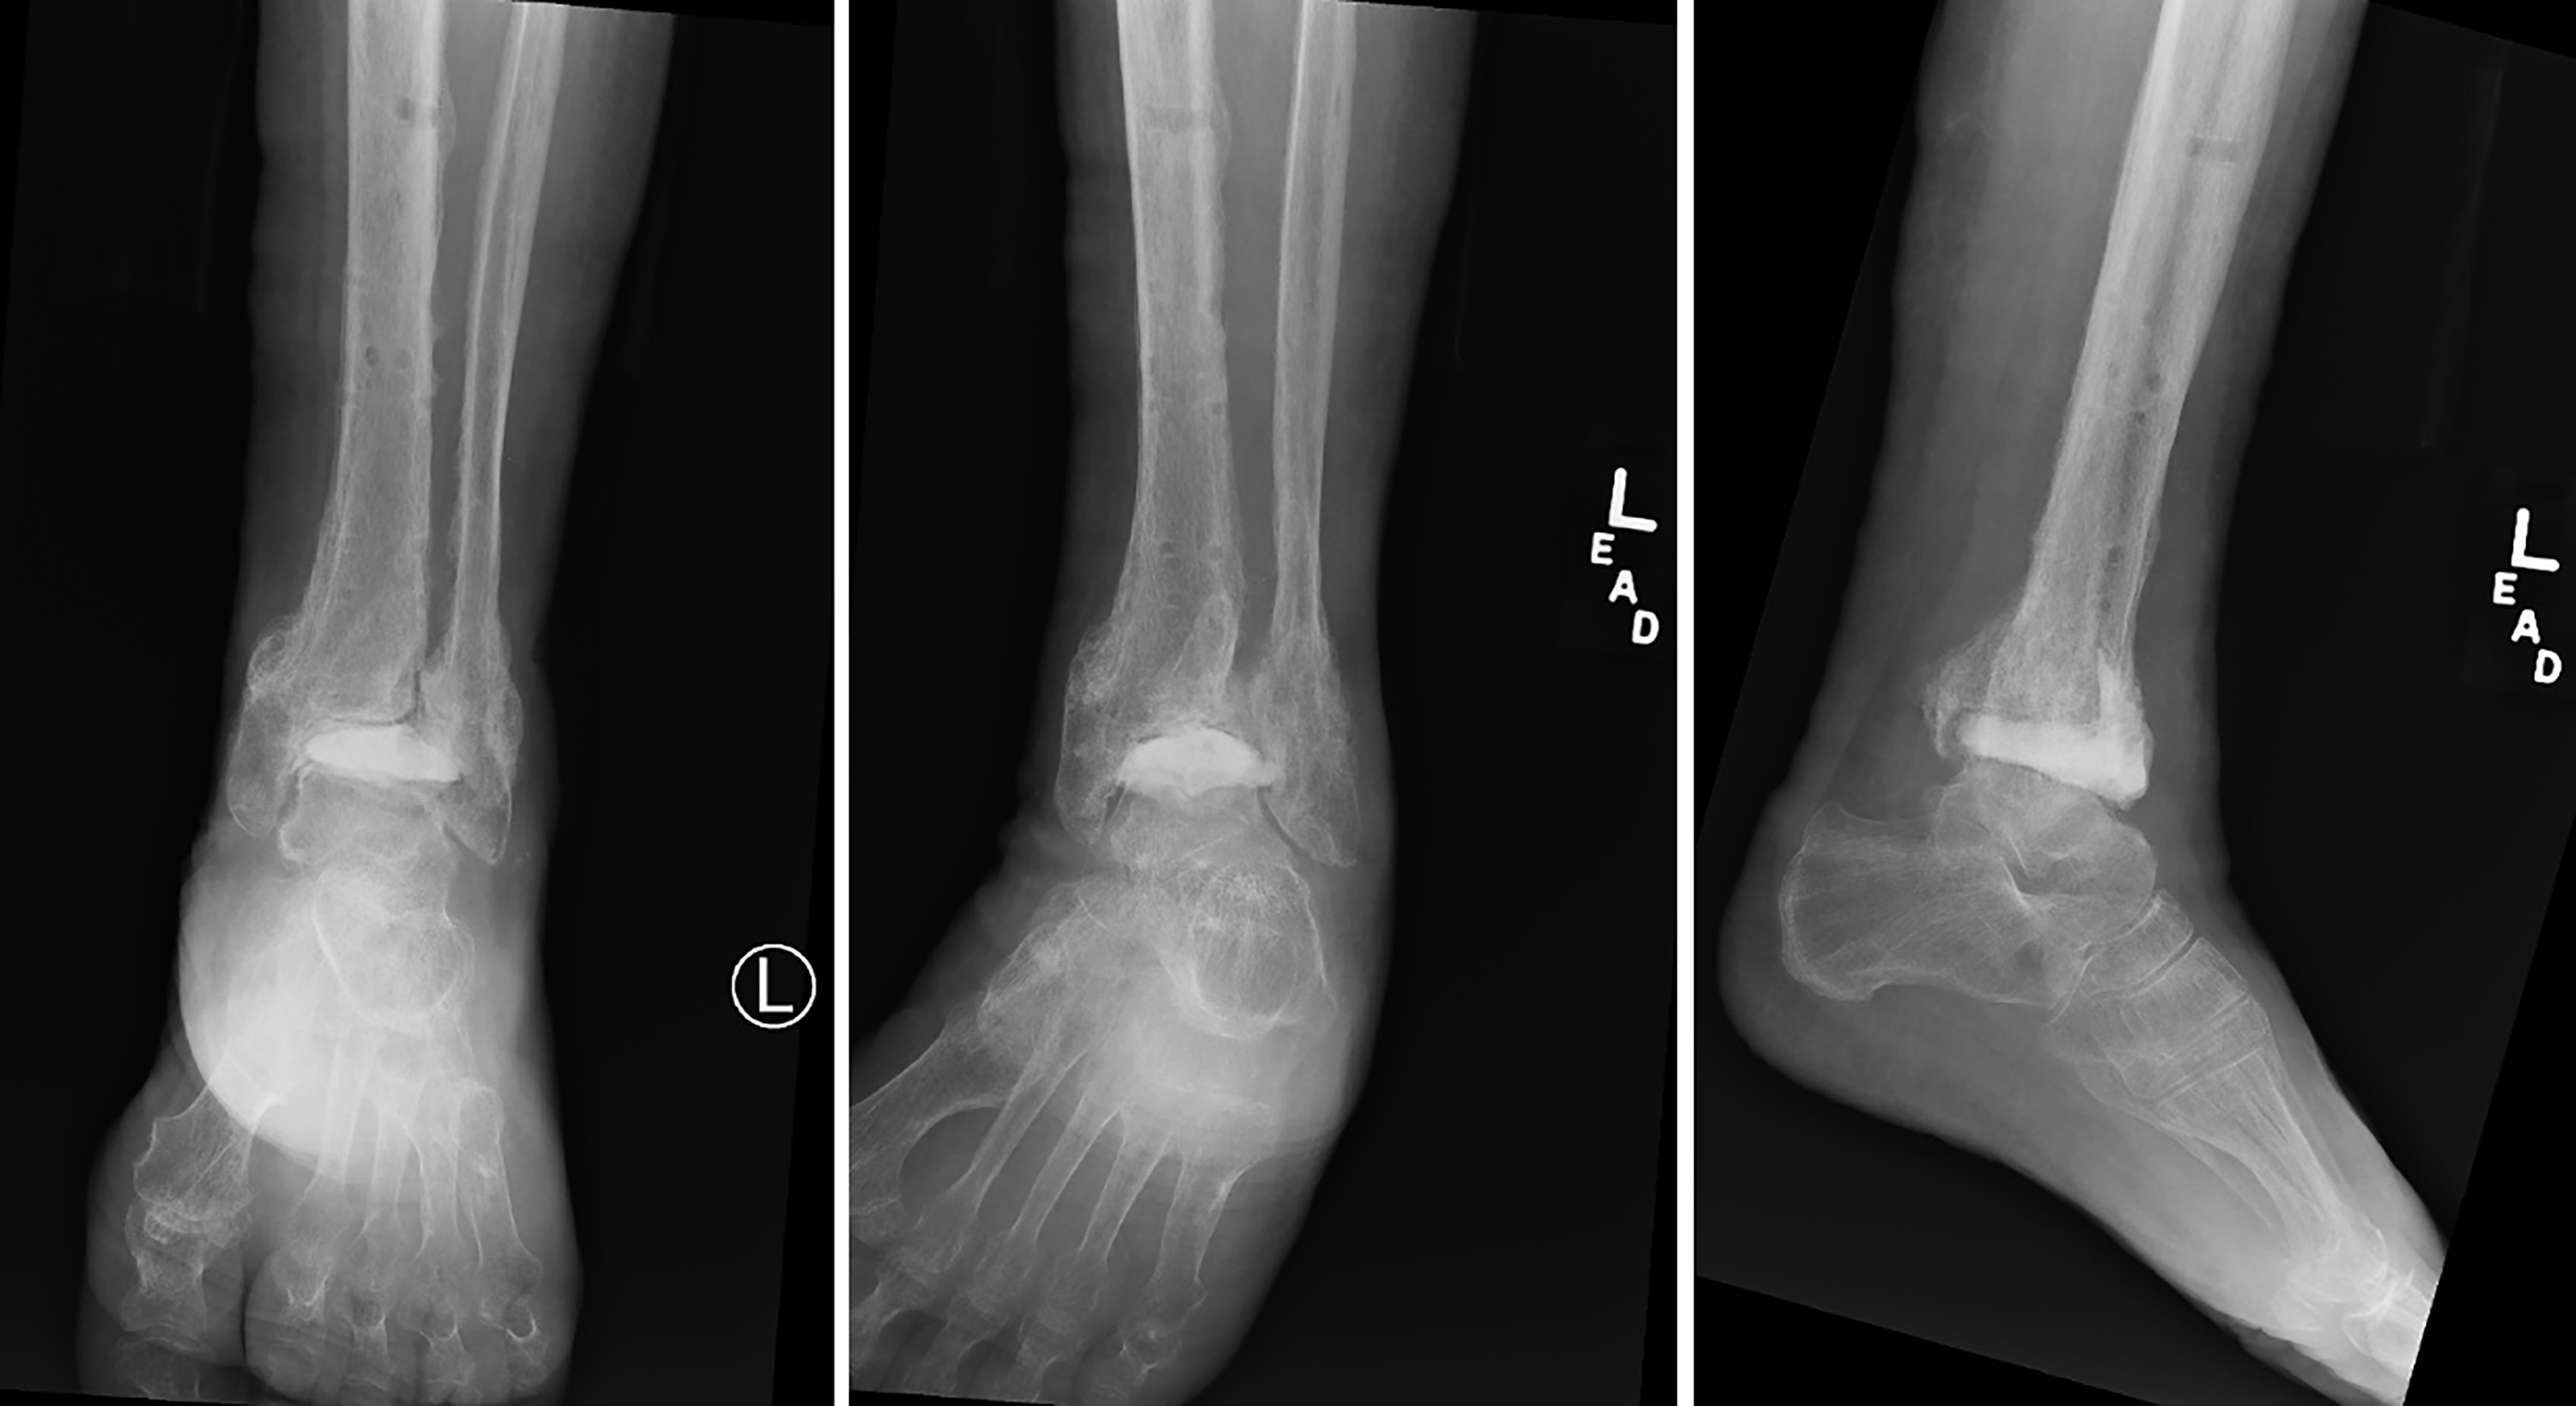

On physical examination, she was noted to be neurovascularly intact. There was nonpitting edema with a moderate joint effusion encompassing the anterior ankle. On inspection, a 10-cm cicatrix was apparent to the anterior ankle and a superficial abscess with central sinus tract noted to the anterolateral ankle (Fig. 1). Ankle range of motion was noted to be restricted with grating and crepitation present. There was tenderness to palpation of the distal tibia, fibula, and medial and lateral ankle gutters. Preoperative radiographs revealed an axial screw fixation of the fibular fracture with periosteal bone formation, as well as an anterolateral buttress plate with evidence of subsidence of the distal tibia with intra-articular screw migration to the talocrural joint (Fig. 2). The tibial fracture appeared consolidated, but hardware lucency along the metaphysis suggested chronic osteitis. Three-phase bone scan and single-photon emission computed tomography revealed focal radiotracer uptake to the left ankle suggestive of osteomyelitis (Fig. 3).

Figure 2. Preoperative radiographs demonstrating significant subsidence of the tibial buttress plate with axial screw fixation of the fibula.